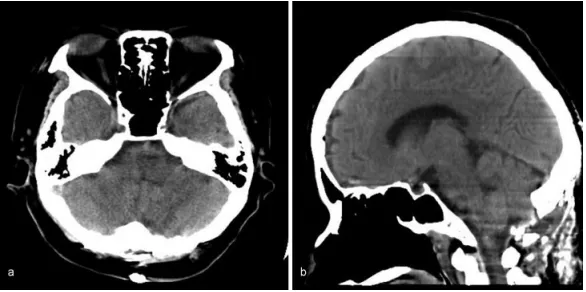

MRI检查没找到出血原因,既不是海绵状血管瘤,也不是动静脉畸形,医生确诊为高血压原发性延髓出血。通过持续输着降压药,萨拉的血压慢慢降了,可唿吸抑制一点没好转。

图:磁共振图像显示出血没有明显的病理原因,(a)T2加权(b)T2加权。